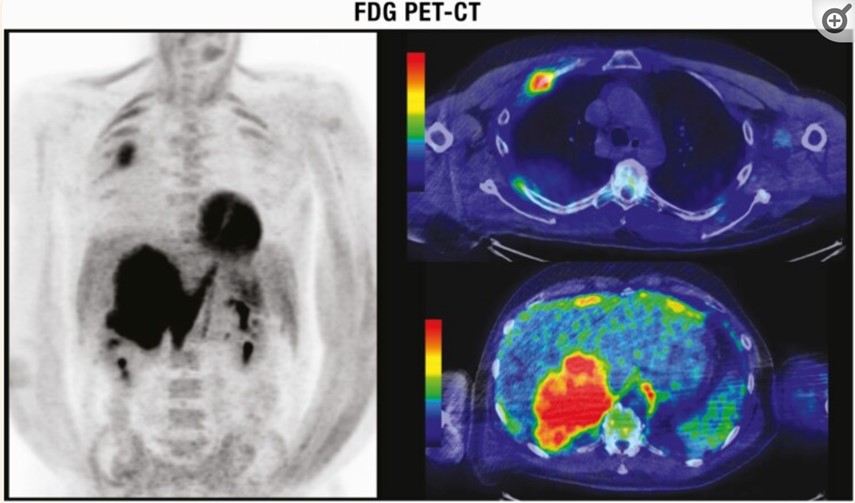

Tomografía por emisión de positrones (PET)

Es una modalidad de medicina nuclear que proporciona imágenes tomográficas cuantitativas después de la inyección intravenosa de un radiotrazador emisor de radiación beta más (positrón) (18-flúor) utilizado para etiquetar la 2-desoxi-D-glucosa que renderiza Fluoro-Desoxiglucosa ([18F]FDG). Tanto la glucosa como la desoxiglucosa entran en las células a través de transportadores de glucosa transmembrana y se someten a fosforilación, pero mientras que la glucosa sufre una mayor descomposición enzimática, la desoxiglucosa queda atrapada en los compartimentos intracelulares. Las células cancerosas tienen una mayor necesidad de glucosa y, por lo tanto, ingieren más glucosa y desoxiglucosa que las células normales. Sin embargo, la FDG no es un marcador específico para las células cancerosas, sino solo un marcador para aumentar el metabolismo de la glucosa. Por lo tanto, la absorción también puede aumentar en las células con un mayor requerimiento de energía debido a condiciones distintas del cáncer, por ejemplo, la infección activa.

La medición cuantitativa de las concentraciones de [18F]FDG dentro de los tejidos proporciona el índice de medición clínica más utilizado, el valor de captación estándar (SUV), que compara la intensidad de la captación de 18F en la lesión suprarrenal con la captación promedio de todo el cuerpo. Los valores estándar de absorción se han utilizado para diferenciar entre lesiones suprarrenales benignas y malignas. El FDG-PET por sí solo tiene una alta sensibilidad para la detección de cambios metabólicos, pero su resolución espacial para la localización anatómica es pobre. La solución es una fusión de hardware entre PET y CT (PET/CT) que permite la adquisición simultánea de datos de PET y CT. En la práctica clínica, esto implica inyectar a los pacientes con trazadores de FDG al menos una hora antes del inicio de la PET/CT combinada. Además de su potencial de diagnóstico para discriminar entre lesiones suprarrenales benignas y malignas, la FDG-PET/CT puede ayudar, en caso de sospecha de carcinoma adrenocortical o feocromocitoma, a identificar metástasis y, en caso de sospecha de metástasis suprarrenal, a detectar el tumor primario.

Tiene una alta precisión diagnóstica para la caracterización de las masas suprarrenales con una sensibilidad agrupada del 91% y una especificidad del 91% en un metaanálisis reciente de 29 estudios en los que participaron 2421 pacientes.(25) Esta técnica es más cara y está menos disponible que la tomografía computarizada y la resonancia magnética, pero puede ayudar a discriminar la enfermedad metastásica de las masas benignas en pacientes con malignidad conocida(26) (Figura 3). Una limitación es que las lesiones suprarrenales benignas, particularmente los adenomas funcionales y los feocromocitomas no metastásicos, pueden ser FDG positivos.